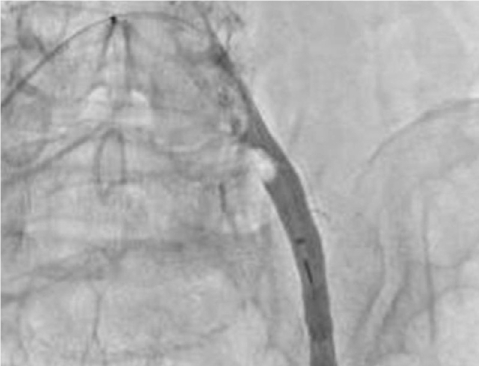

Computed tomographic (CT) angiography of the left lower extremity showed total occlusion of the proximal left common iliac artery (Fig. 1). Initially, we performed intra-arterial thrombolysis with urokinase 200,000 units for 1 hour. Follow-up angiography revealed antegrade flow with large residual thrombi (Fig. 2), so we decided to perform a percutaneous mechanical thrombectomy through the ipsilateral femoral artery using the OASIS™ thrombectomy system (Medi-Tech/Boston Scientific, Watertown, MA) (Fig. 3). Immediate post-procedural angiography demonstrated almost complete patency of the previously occluded artery. Follow-up CT angiography 14 days later showed a normal left common iliac artery (Fig. 4).